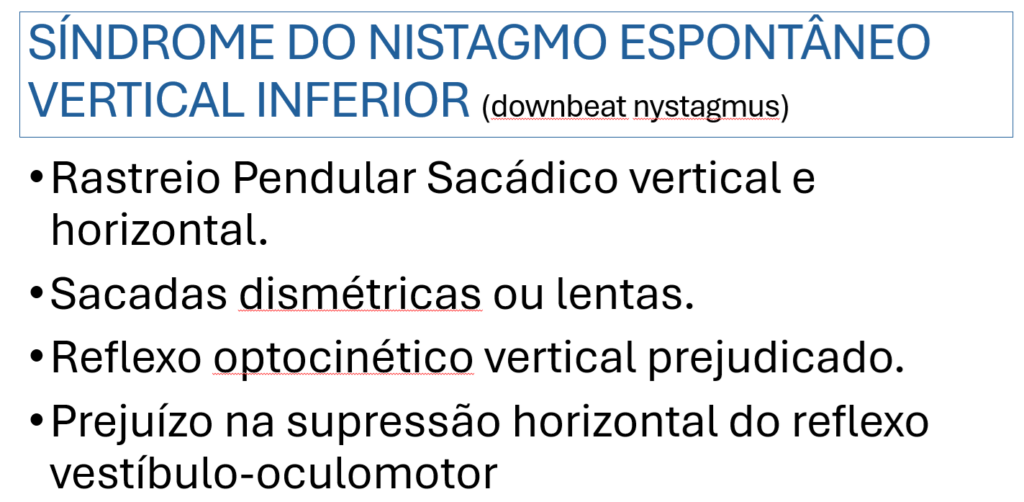

No exame físico desarmado apresenta nistagmo espontâneo vertical inferior em todas as posições cardinais do olhar, com maior intensidade nas miradas laterais:

Do ponto de vista sindrômico, apresenta a Síndrome do Nistagmo Espontâneo Vertical Inferior.

O nistagmo espontâneo vertical inferior (NEVI) é a forma mais comum de nistagmo adquirido.

Pacientes com NEVI como essa paciente, podem desenvolver a oscilopsia vertical e/ou visão borrada. Essa oscilopsia piora nas situações em que os olhos abaixam como em leituras (o nistagmo aumenta).

O NEVI obedece a Lei de Alexander, uma vez em que intensifica-se na direção da componente rápida e lentifica-se na direção da componente lenta. Intensifica-se no olhar para baixo e diminui ou desaparece no olhar para cima.